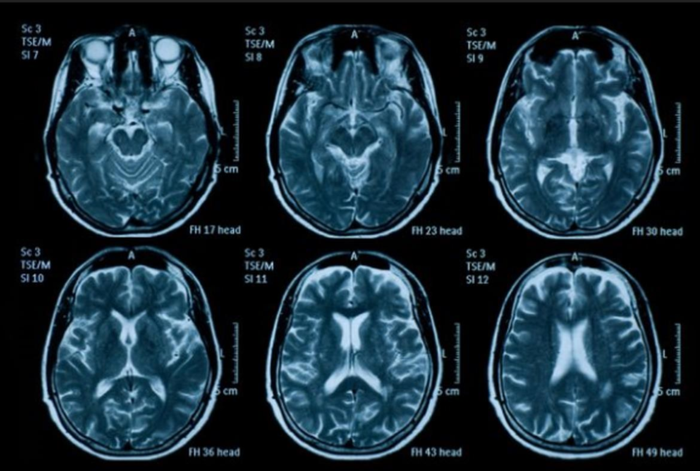

X quang: là chuyên ngành sử dụng hình ảnh y khoa để chẩn đoán và điều trị bệnh có thể thấy được trong cơ thể người. Kỹ thuật chẩn đoán hình ảnh hiện nay rất đa dạng không chỉ giới hạn ở tia X, các công nghệ như siêu âm, chụp cắt lớp vi tính (CT), y học hạt nhân gồm chụp xạ hình cắt lớp positron (PET), và chụp cộng hưởng từ (MRI) được sử dụng trong chẩn đoán và điều trị bệnh. Từ năm 1970, các công nghệ như tia X, quét CT và MRI đã cứu được khoảng 25 triệu mạng sống.